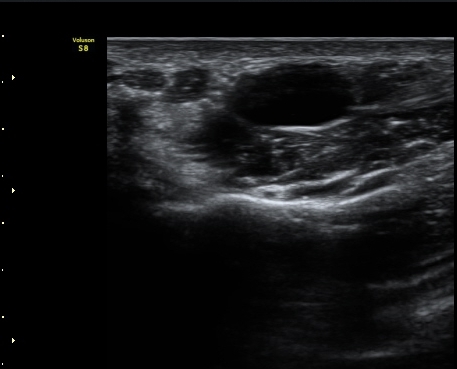

ŽÃËÀÚ¸¦ Á¶±Ý ´õ ¸»´ÜÀ¸·Î À̵¿ÇÏ´Ï Á¤Áß½Å°æ ½ÉºÎ¿¡ Àú¿¡ÄÚ ³¶Á¾ÀÌ °üÂûµÇ°í(»çÁø 4),

³¶Á¾ÀÌ Á¤Áß½Å°æ ¼öÁö °¡Áö¸¦ ¾Ð¹ÚÇÏ´Â ¸ð½ÀÀÌ °üÂûµÈ´Ù(»çÁø 5, 6, 7).